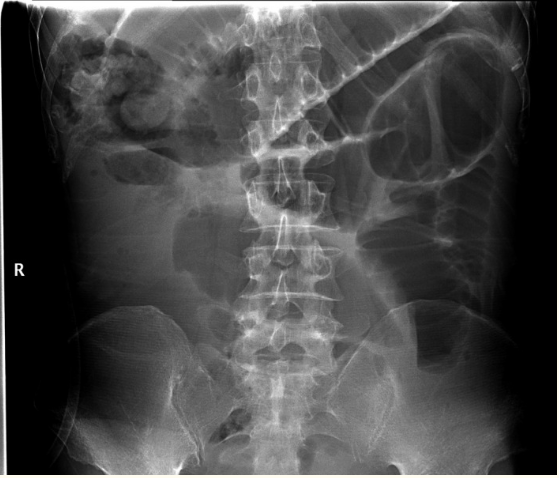

患者进行了4个疗程的化疗(5-氟尿嘧啶/奥沙利铂),随后复查了腹部CT和X线,提示肿瘤引起肠梗阻,如图3所示

图3 立位腹平片提示不完全性肠梗阻